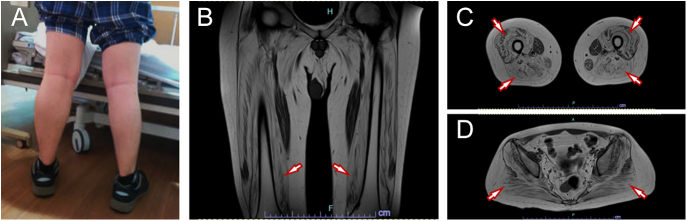

Summary: Duchenne and Becker muscular dystrophy (DMD/BMD) are genetic disorders characterized by progressive muscle degeneration due to alterations of the dystrophin protein. The degeneration of skeletal muscles and subsequent replacement with adipose tissue affect motor function as well as insulin sensing and glucose uptake in skeletal muscle, leading to the impairment of systemic glucose tolerance. Although several cases of glucose intolerance accompanied by DMD/BMD have been reported, the development of diabetes is clinically rare in adult cases with DMD/BMD. A 25-year-old man with BMD developed diabetes after receiving heart transplantation due to dilated cardiomyopathy and being on immunosuppressive drugs. Although he did not show evident glucose intolerance before heart transplantation, he demonstrated decreased β-cell function. Despite the shared background of BMD, his older brother, who had not undergone heart transplantation, showed only slightly impaired glucose tolerance and preserved β-cell function. The difference in glucose tolerance in the siblings with BMD clarifies the critical role of β-cell dysfunction in the development of diabetes in individuals with compensatory increasing demand for insulin such as DMD/BMD. In addition, the clinical importance of vigilance for post-transplant diabetes in BMD cases with immunosuppressive agents should be noted.

Learning points: Muscle disease such as Duchenne and Becker muscular dystrophy (DMD/BMD) impairs motor function as well as insulin sensing and glucose uptake in skeletal muscle. While the development of diabetes is very rare in adult cases with DMD/BMD, diabetes can develop with concomitant loss of beta-cell function. Vigilance for post-transplant diabetes in people with muscle disease as well as DMD/BMD with immunosuppressive agents is clinically important.